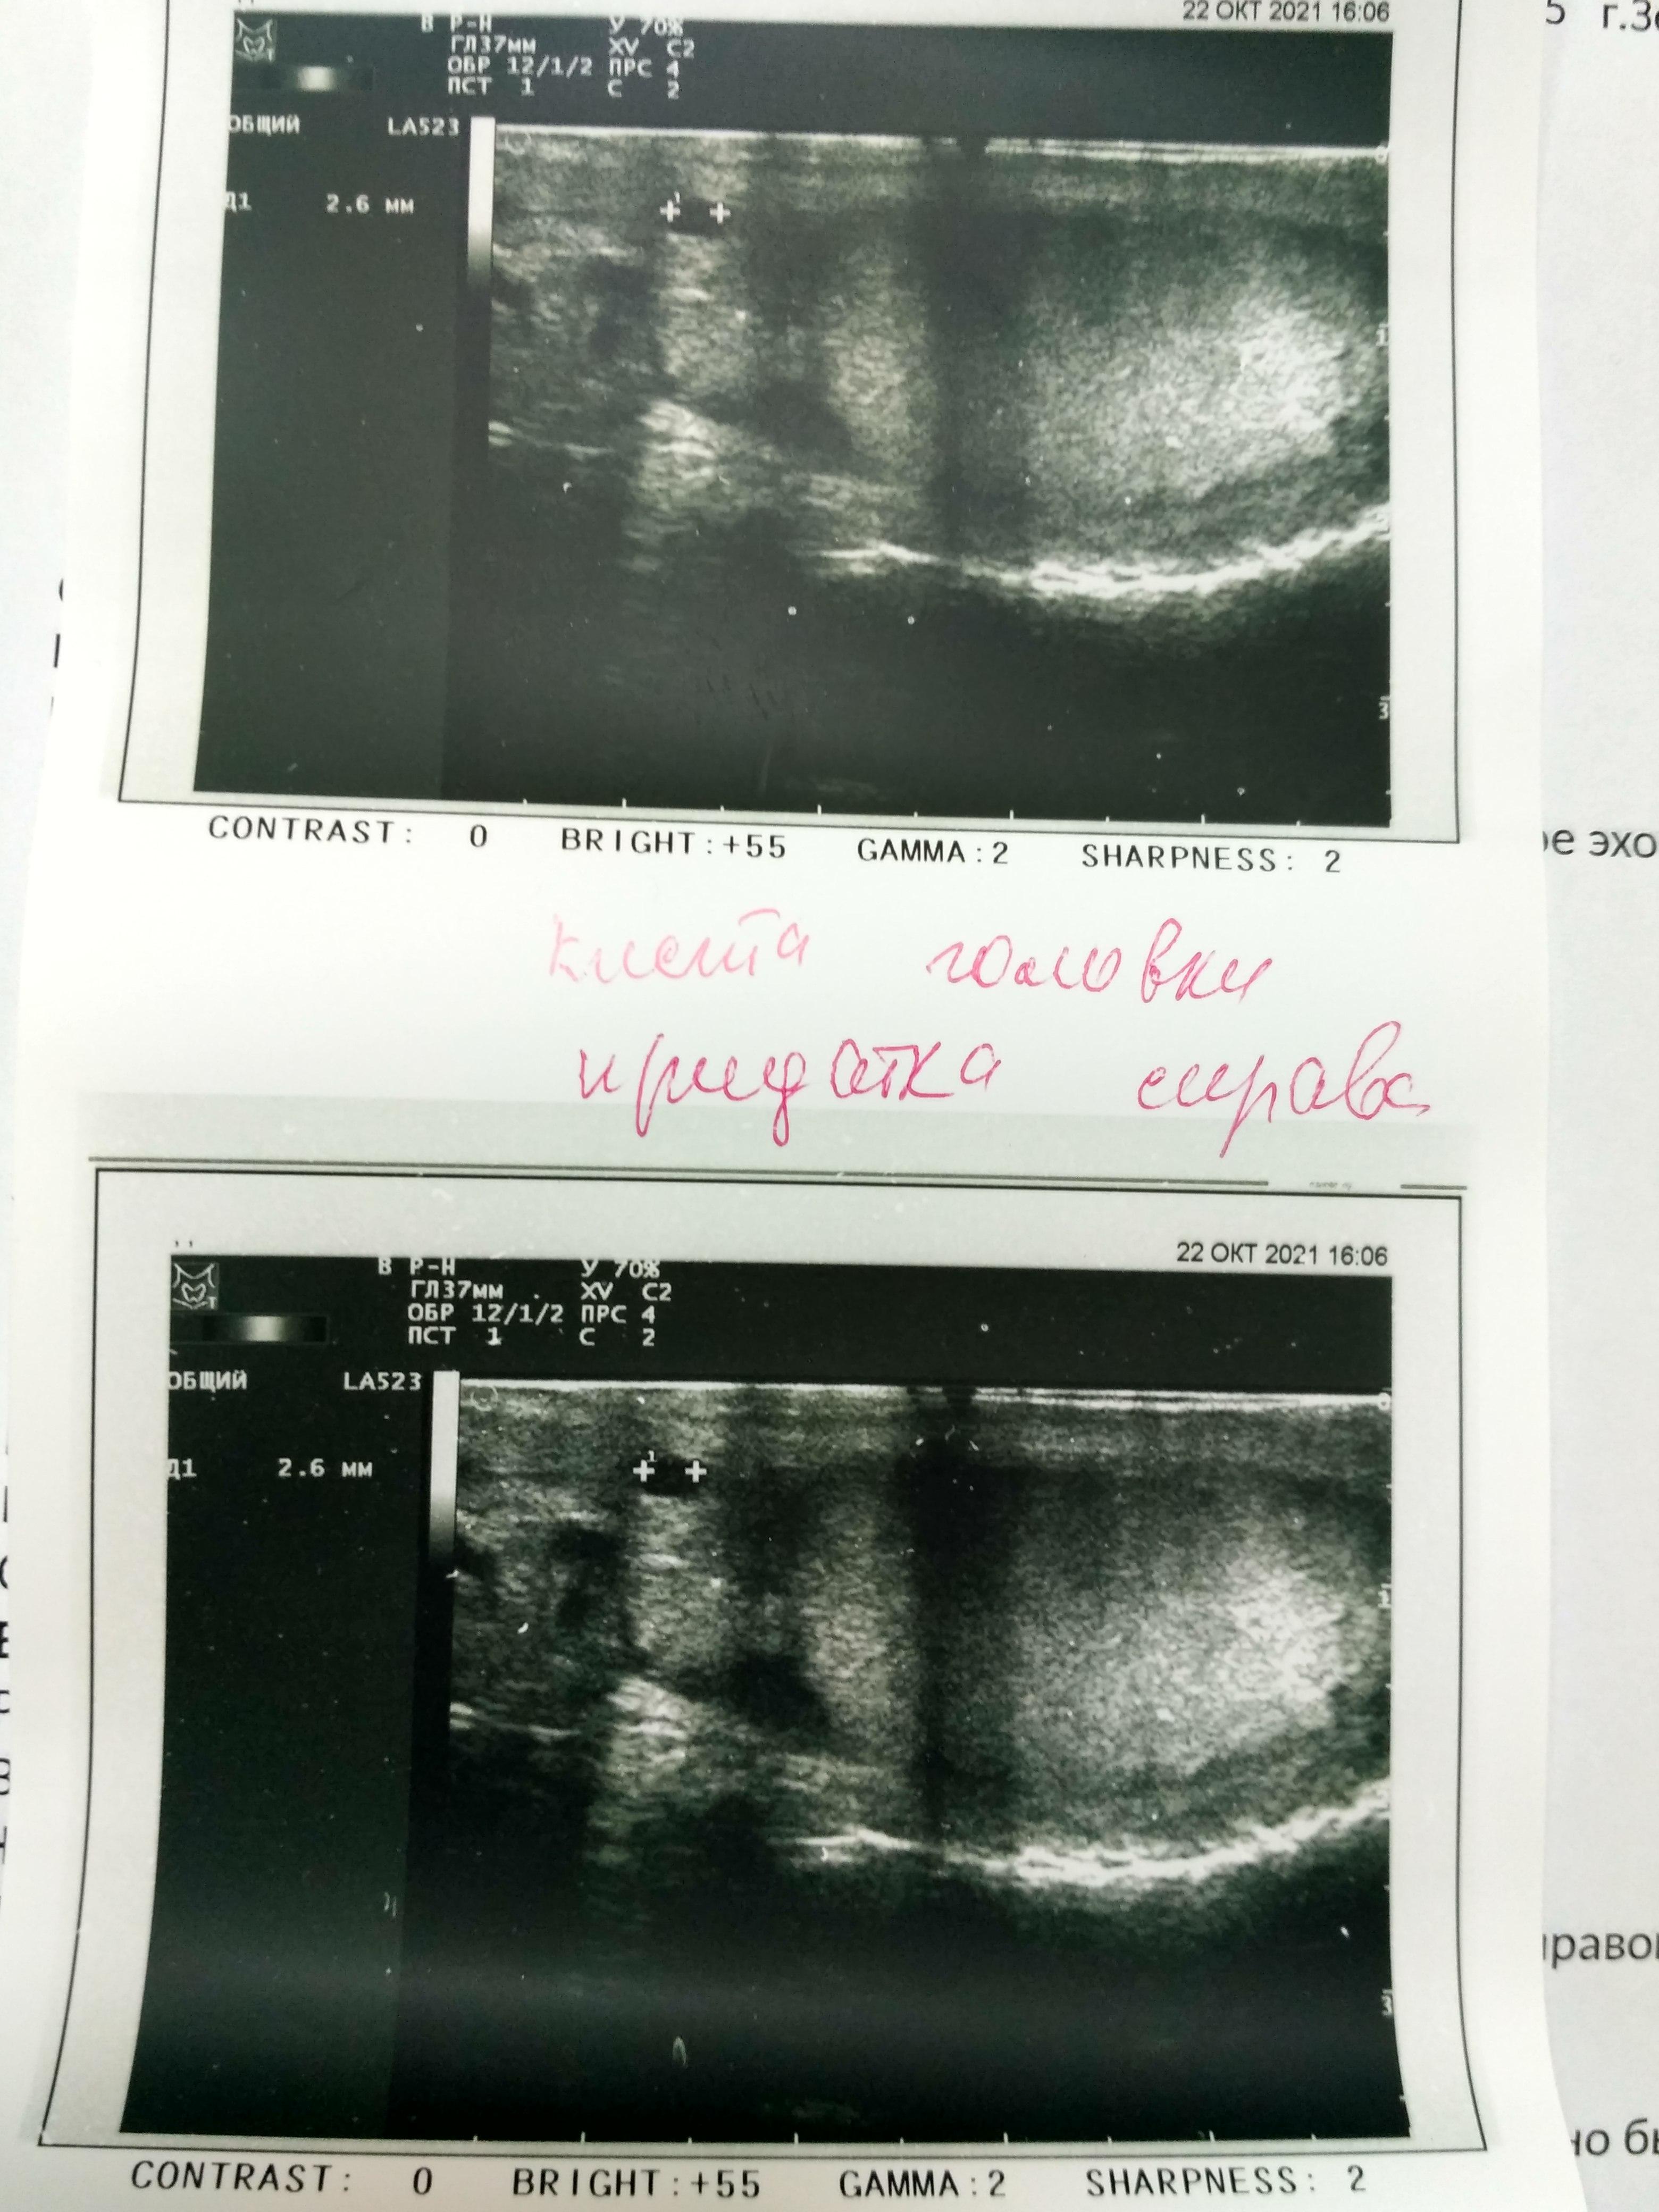

И сделал УЗИ. Не могли бы сказать все ли там хорошо? И на что обратить внимание?

По результатам УЗИ почек - выявлено образование левой почки (киста?). По этому поводу я бы рекомендовала сделать МСКТ почек с контрастом( обсудите этот вопрос с Вашим урологом) - для уточнения характера образования.